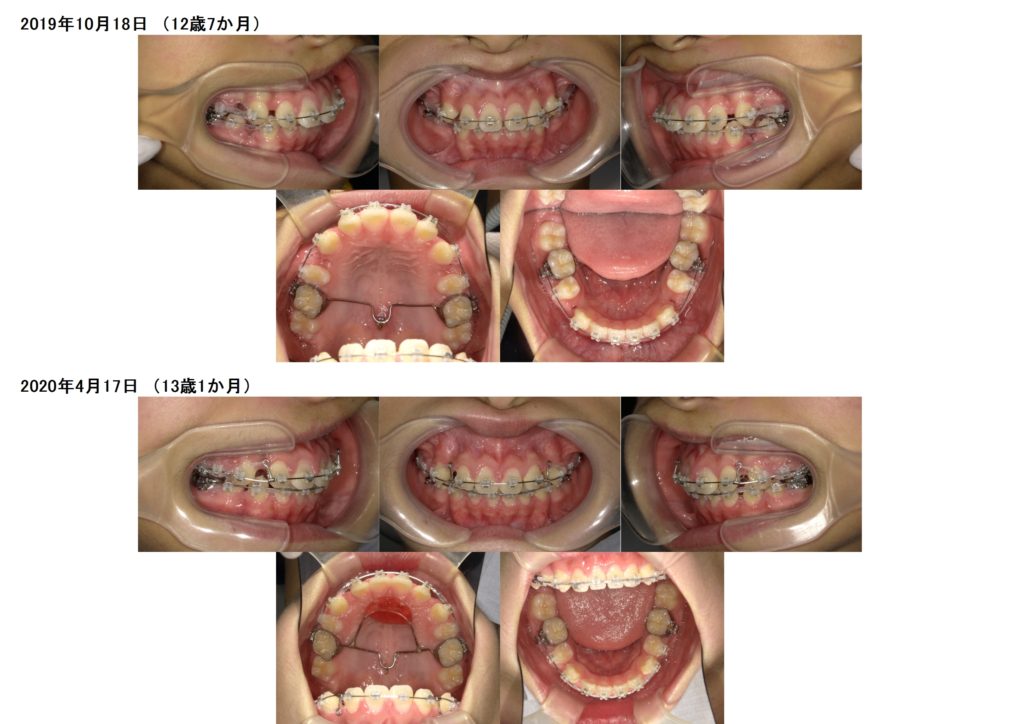

↑この患者様は上下の歯を2本ずつ抜歯しています。

上の顎にアンカースクリューを使用し、抜歯した際に6番目の歯が寄ってこないためにしています。

このように土台を整えつつ、ブラケットを使用し調整をしていきます。

奥歯の噛み合わせを確立したら、あとは前歯部の噛み合わせを合わせ引っ込めていきますよ

隙間が埋まったら治療が終わりです☆